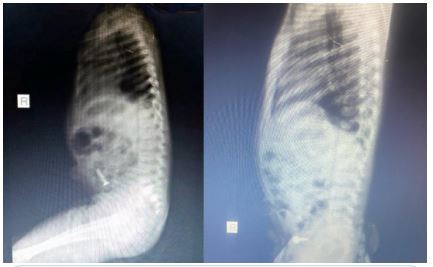

She presented with a plain abdominal radiograph which showed a FB (nail) in the body of the stomach (Figure 1) This was done about 6 hours prior to the presentation at our facility. A repeat radiograph done at the presentation showed the FB (nail) at the region of the terminal ileum (Figure 2). She was commenced on nil per oral, intravenous fluids and monitoring (clinical and radiological). She had two additional plain abdominal radiographs, (Figure 3, 24 hours on admission) and (Figure 4, on day 3). The vital signs remained stable and the abdominal examinations remained equivocal throughout the period of admission. She was discharged following a repeat radiograph which showed no evidence of FB in the GIT.

Figure 3: AP + Lateral view of plain abdominal radiograph. (24 hours admission).

Figure 4: AP view of plain abdominal radiograph (Day 3).